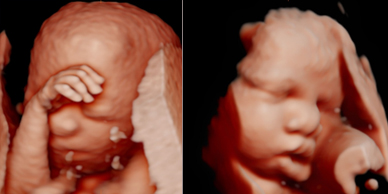

Skanda Advanced Ultrasound Scan Centre starts right from the onset of pregnancy. Our Fetal Medicine experts are concerned with the health of the fetus at every stage – monitoring growth & development; predicting, detecting & managing any complications; and treating congenital disorders & anomalies in the womb itself.